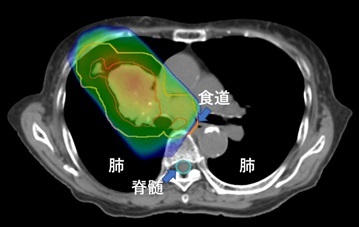

III期肺がん。IMRTを用いて正常の肺や食道、脊髄の線量を減らしている。